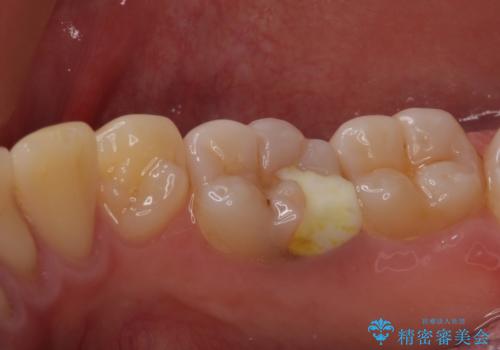

- 下顎左右奥歯に虫歯で痛みを感じるとのことで来院された患者様です。

むし歯が大きく、神経を取り除く可能性があることを理解いただいた上で虫歯を取り除き、その後はオールセラミッククラウンにて補綴することとしました。